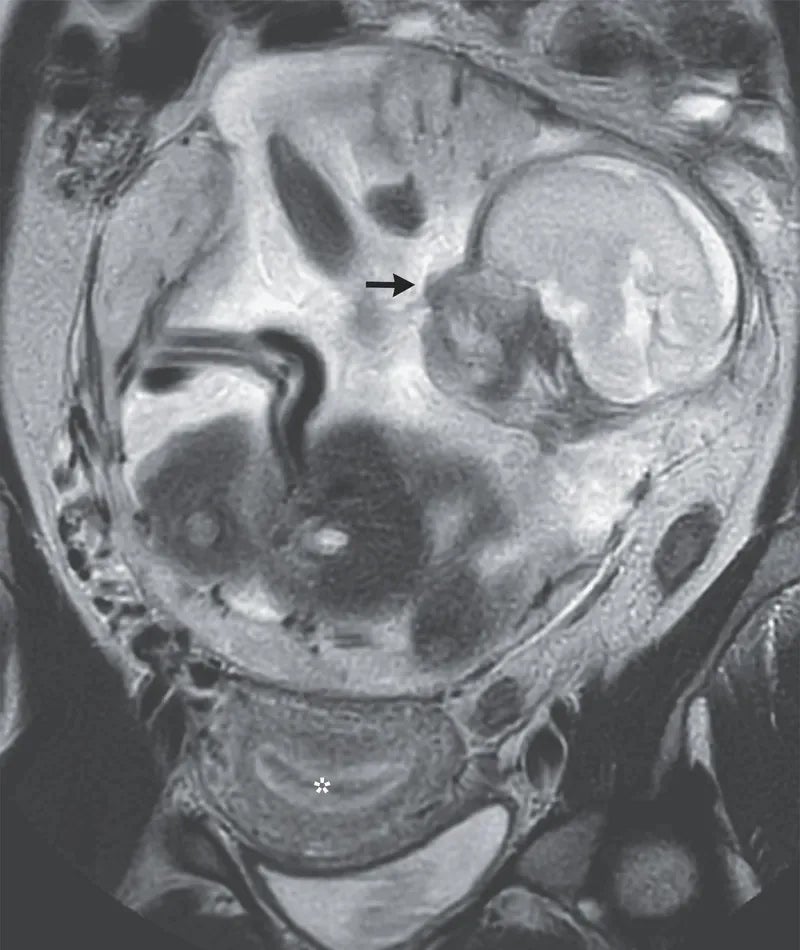

Viel schockierender für die Schwangere als auch die Ärzte war das Ergebnis der zweiten Untersuchung: Ihr Baby befand sich in ihrem Darm!

Ein außergewöhnliches Phänomen, das zwar nicht ganz neu, jedoch äußerst selten ist. Medizinisch spricht man von einer abdominalen Eileiterschwangerschaft. Dabei nistet sich eine befruchtete Eizelle außerhalb der Gebärmutter in der Bauchhöhle ein. Nur bei einem Prozent aller Eileiterschwangerschaften ist das der Fall.

Statt in der Gebärmutter hat sich die Eizelle in der Bauchhöhle eingenistet

In diesem Fall hatten Mutter und Kind jedoch Glück. Nach der Diagnose wurde die Frau in ein Universitätskrankenhaus verlegt, wo das Baby in der 29. Woche entbunden wurde.